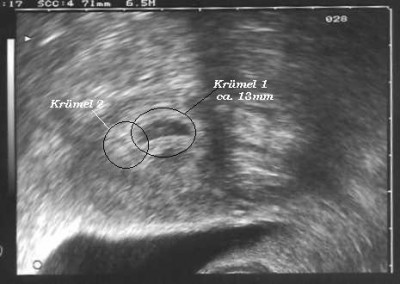

ich bin ganz aufgeregt, wir kommen gerade vom US beim Prof. er hat eine Fruchthöle gesehen mit Inhalt, er meinte er sieht den Dottersack und die entwicklung wäre gut (Zeitgemäß). Stellt Euch vor er hat noch eine 2. Fruchthöhle gesehen, die ist etwas kleiner konnte aber nicht sagen ob da auch was drin ist. Vieleicht bekommen wir ja doch 2 :baby: :baby: :juhu: :juhu: :juhu: Ich kann es garnicht glauben, es wäre so schön. Wobei ich schon Angst vor einer Zwillingsschwangerschaft habe, weil da doch mehr pasieren kann, bzw. die Babys meisten früher kommen.

Dateianhänge

2ab.JPG